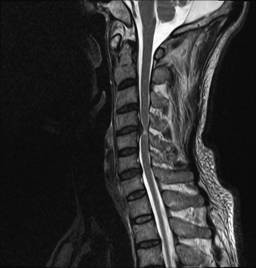

中年男性41歲,因“行走不便2年,加重伴雙手麻木2周”之主訴入院,癥狀主要為:頸部疼痛、僵硬,雙下肢無力、行走不穩(wěn),雙手麻木,協(xié)調(diào)性差,右手握筆困難。入院查體:步態(tài)不穩(wěn),C3-C7壓痛、叩擊痛,肢痛溫覺減退,雙上肢肢肌力5-級,雙下肢肌力4-級,肌張力增高,雙下肢腱反射亢進(jìn),病理征(+),行頸前路小切口突出椎間盤切除、前路頸椎橋形鎖定植骨融合(ROI-C假體),無需前路鋼板,術(shù)后四肢麻木明顯緩解,右上肢精細(xì)動作明確增強(qiáng),可寫字,行走不穩(wěn)消失,肌力基本正常,頸部活動度無明顯受限。(圖1、圖2)

圖1:術(shù)前頸椎MRI提示頸椎退行性變,C4/5椎間盤突出、脊髓出現(xiàn)高信號改變,C4硬膜囊受壓變形。